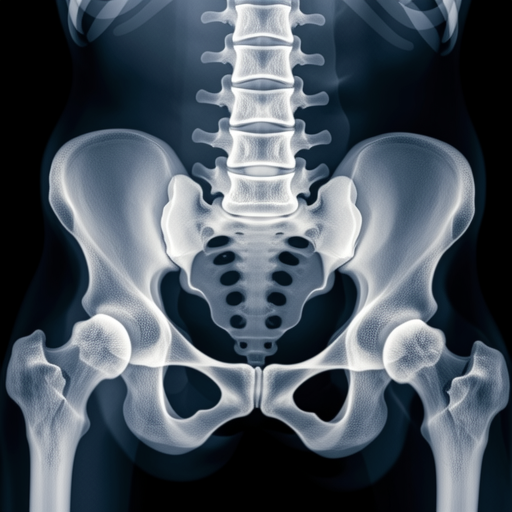

Canine hip dysplasia radiographic evaluation

Figure 2: Radiographic assessment of canine hip joints for dysplasia evaluation

Veterinary radiography serves multiple diagnostic purposes across various specialties. Orthopedic evaluations represent approximately 45% of all veterinary radiographic studies, followed by thoracic imaging (30%) and abdominal studies (25%), according to data from the UC Davis Veterinary Medical Teaching Hospital.